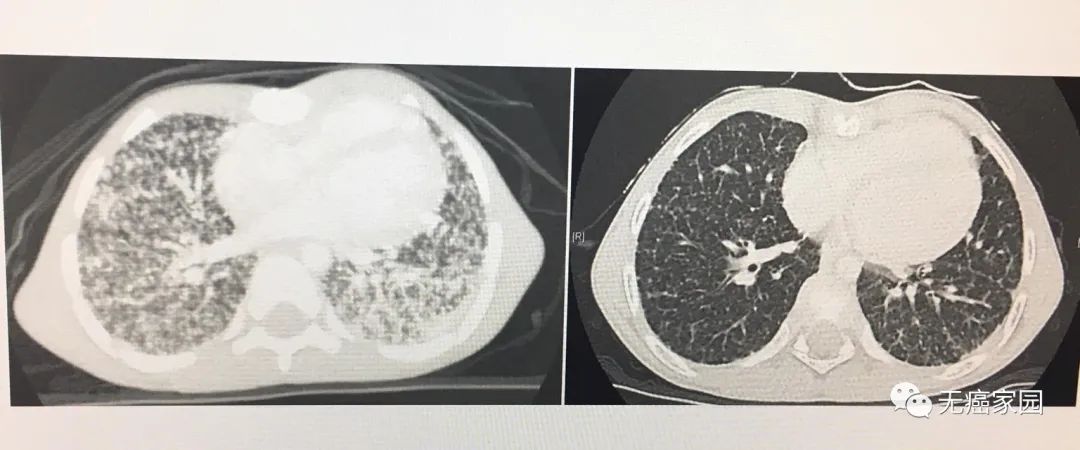

此名患者是一位71岁的男性,2018年12月感到吞咽障碍、伴有咳嗽、呼吸困难等症状,3个月内体重减轻20公斤,身体状况不佳,ECOG体力状况评分为3分(生活仅能部分自理,日间一半以上时间卧床或坐轮椅)。患者没有酗酒、吸烟史,也未得过肿瘤,食管胃十二指肠镜检查显示在食管中断有狭窄性食管癌,CT显示双侧肺转移,超声检查和CT显示多发性肝转移。食管肿瘤活检和经超声检查控制肝活检诊断确认。

经过FoundationOne CDx测试等常规组织学检查,确定患者为转移性鳞状细胞食管癌。测序结果中显示肿瘤组织中含有NTRK1基因突变,遂从2019年2月4日开始服用拉罗替尼治疗,患者接受2×100毫克的标准剂量,治疗期间未发生副作用。

患者常规组织学检查测序结果

患者治疗前于2019年1月4日完成螺旋CT扫描,起初显示出多处肺和肝转移。在治疗后评估ECOG体力状况评分为1,并且体重增加9公斤,能够离开医院且生活自理。2019年4月17日进行的随访活检检查(食管胃十二指肠镜检查)证实了患者的食管再无肿瘤。

患者食管支架治疗前用拉罗替尼及治疗后6周食管胃十二指肠镜检查结果